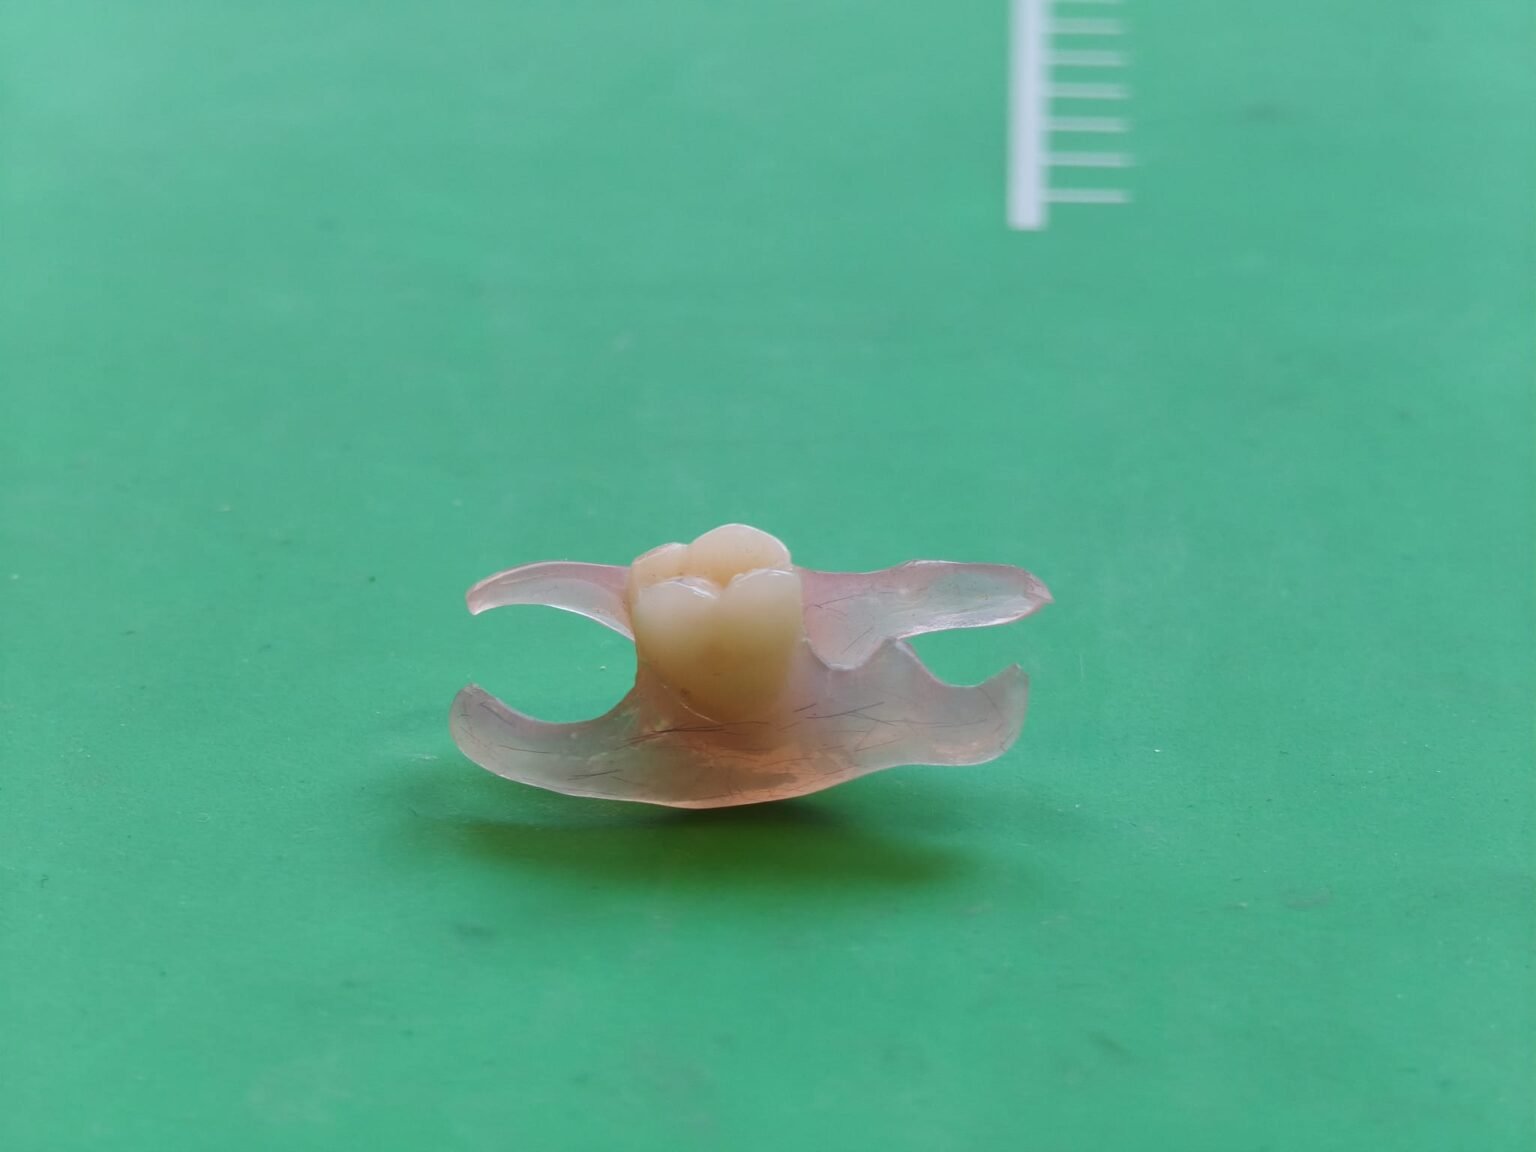

Therapeutische Schienen kommen dann zum Einsatz, wenn funktionelle Abläufe gezielt geführt oder entlastet werden sollen. Eine zuverlässige Wirkung entsteht nur, wenn Kontaktverhältnisse, Gleitbewegungen und die Ausrichtung der Schiene exakt auf die individuelle Situation abgestimmt sind. Deshalb legen wir besonderen Wert auf klar definierte Kontaktzonen und eine gleichmäßige Druckverteilung, die die Muskulatur entlastet und störende Interferenzen reduziert.

Auch die Gestaltung der Führungsflächen spielt eine wichtige Rolle: Sie wird so ausgeformt, dass sie physiologische Bewegungsmuster zulässt, ohne ungewollte Belastungsspitzen zu erzeugen. Der Tragekomfort wird durch eine präzise Randgestaltung unterstützt, damit die Schiene stabil sitzt, nicht einschneidet und über längere Tragezeiten gut toleriert wird.

Durch die Kombination aus funktioneller Analyse und sorgfältiger Ausarbeitung entsteht eine Schiene, die sowohl diagnostisch als auch therapeutisch zuverlässig eingesetzt werden kann – unabhängig davon, ob es sich um Bruxismus, myofasziale Beschwerden oder gelenkbezogene Einschränkungen handelt.